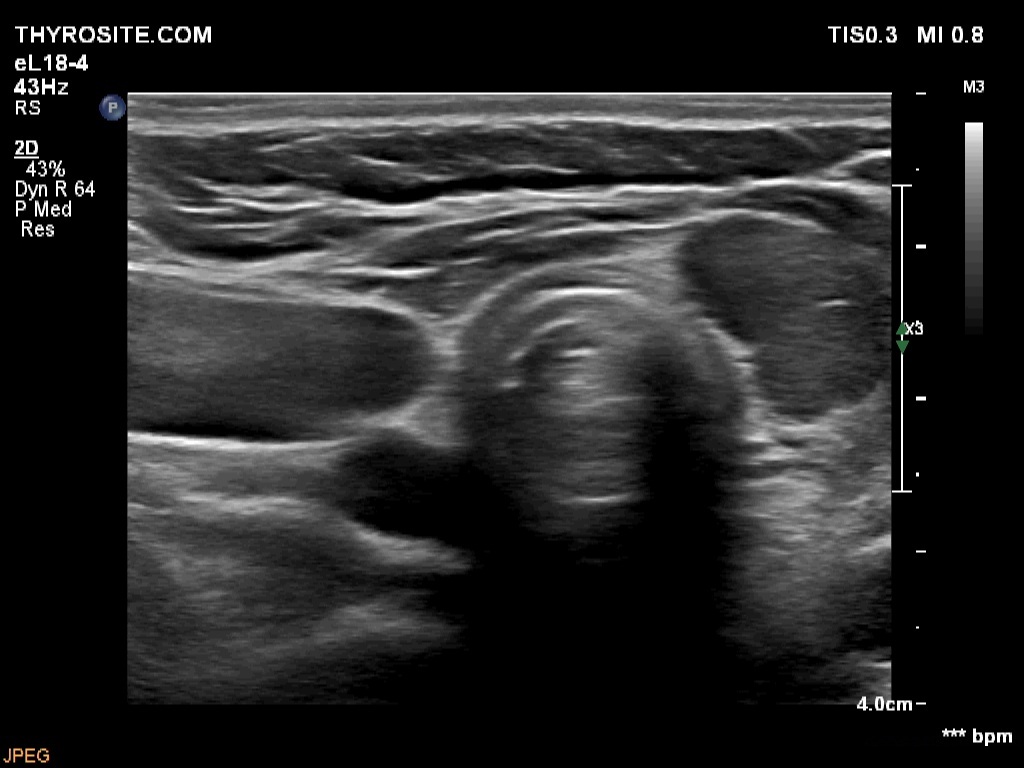

One year after surgery (third row of images)

Clinical data: The patient had no complaints.

Results of blood test: subclinical hyperthyroidism on daily 25 microgram levothyroxine (TSH 0.09 mIU/L, FT4 17.9 pM/L).

Ultrasonography: There was no parenchyma according to the right lobe, while there was a relatively large thyroid tissue in the left lobe. The latter displayed increased vascularization.

TSAb was undetectable. The replacement therapy has stopped. We offered regular follow-up.